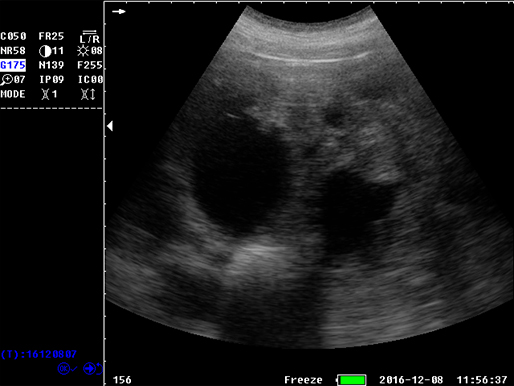

B模式 子宫 牛

B模式 猪孕检

牛未受孕

牛受孕泡

牛受孕35天

猪孕检

猪孕检

猪孕检